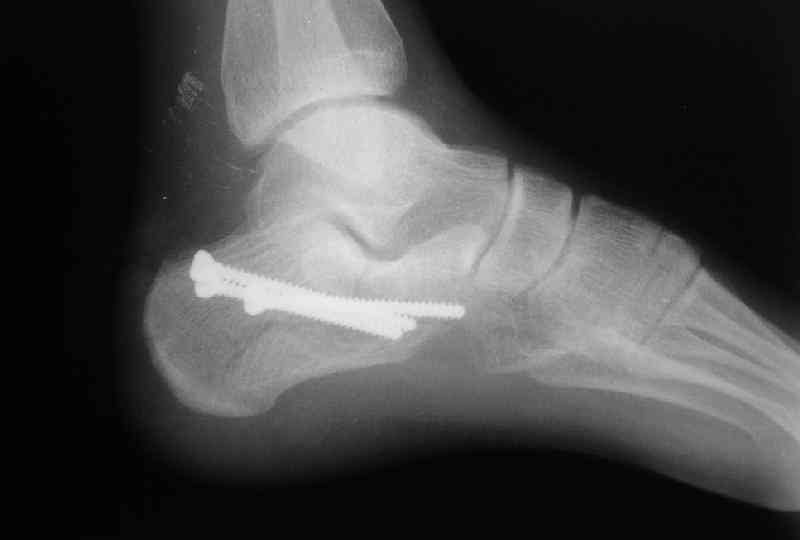

Пяточной пластиной

Открытый и закрытый способы лечения.